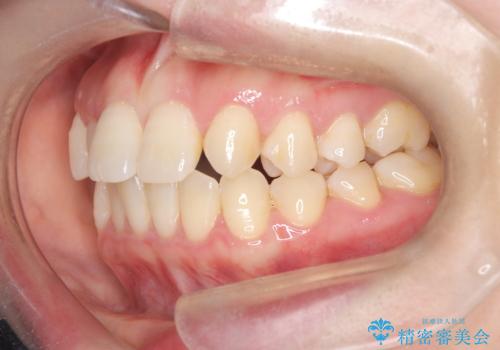

- 歯のデコボコと右上2番の歯の形が気になることを主訴に来院された患者様です。

軽度の叢生(凸凹)であったため、インビザラインのライトパッケージを用いて歯並びを改善しました。その後、右上2番はオールセラミッククラウンにより形態を回復し、審美性を向上させました。